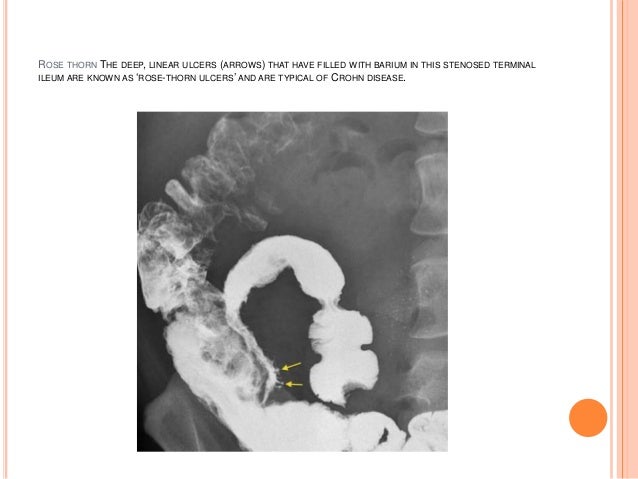

Rose Thorn Ulcers Radiology / It grows next to thorns and can be harvested with any tool, however the axe is the quickest.